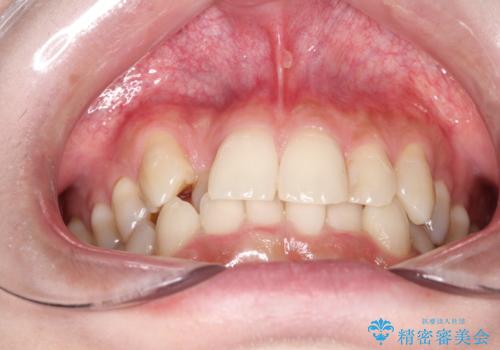

- 八重歯を治したいとのことで来院されました。

右上の犬歯が外側に飛び出して、二番目の歯が内側に入っている状態でした。

上の奥歯を後方に移動させてスペースを確保して、前歯のガタガタを改善する計画としました。